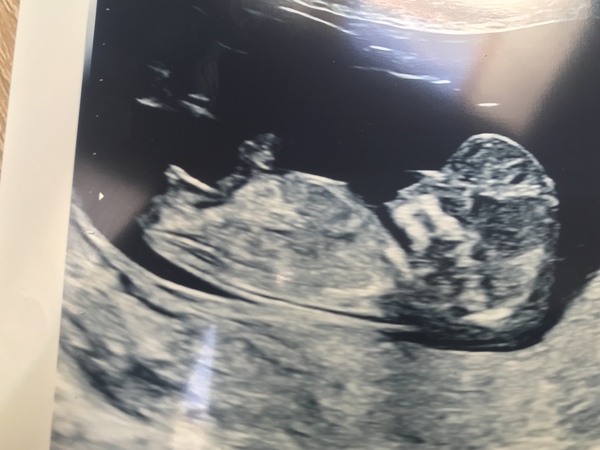

New thread ladies... not long until the first 12 week scans.... mines a week tomorrow!

Lovely scan pic @Fredthespider! 😀

12 week scan is booked for 14th August Grin still feels like ages but it's the day I turn 12 weeks according to LMP so can't ask for more really. And at least I've had a couple of early scans!

Gave in to my anxiety and had an early scan on Sunday. I thought I was 9+6, but that made me 9+1, I was desperately hoping to be further along not less!

Was lovely seeing the heartbeat though, and we could even make out blood flowing along the placenta, amazing

Had my scan. Baby is measuring 12 weeks with a heartbeat however there is something wrong despite seeing baby’s legs, arms, even little fingers and little one had hiccups during scan 😥 they’re not 100% sure but the back of baby’s skull is too large. I don’t know what this means. I’m being referred to Aberdeen and have to have several tests. They mentioned spina bifida and I’m thinking perhaps Down’s syndrome but they have no idea what is actually wrong. I’m so sad, confused and lost. I can’t believe this is happening. Sorry for bringing a downer to the thread, will stick around but may have to consider termination if something is seriously wrong 😭